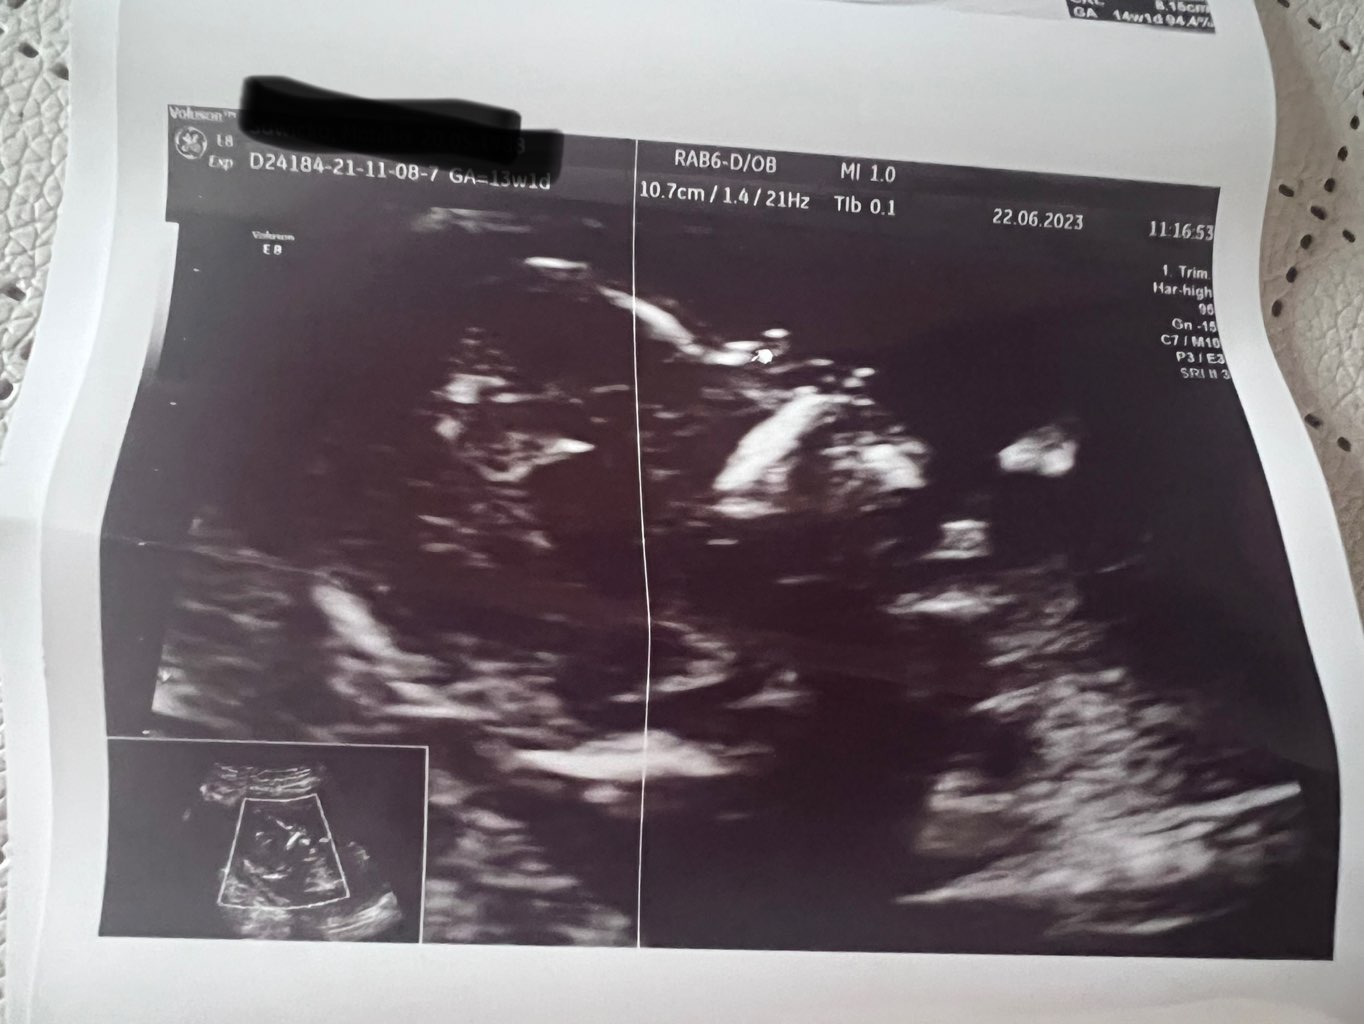

Na obrazie widać ukrwienia przy przepływach na łożysku, ale on nie jest w stanie mi powiedzieć czy to jest cecha wrastającego łożyska, bo nie jest od tego specjalistą. Mam mu dać znać, jak będę po szpitalu co powiedzą (on będzie na urlopie, ale odczytuje maile). Potem przeszliśmy do kości, trochę się musiał nagimnastykować, żeby dobrze ustawić widoczność (pukał mnie po brzuchu i dziecko skakało

) i udało się zrobić zdjęcia z kursorem gdzie widzi i jest kość nosowa (załączam

). Czekamy na wyniki Pappy, powiedział, że w moim wieku i z tym, że w opisie USG prenatalnym jest ta kość brak/hypoplastyczna to pewnie ryzyko będzie podwyższone. Jak już te będą to wtedy będziemy ewentualnie myśleć o amniopunkcji.